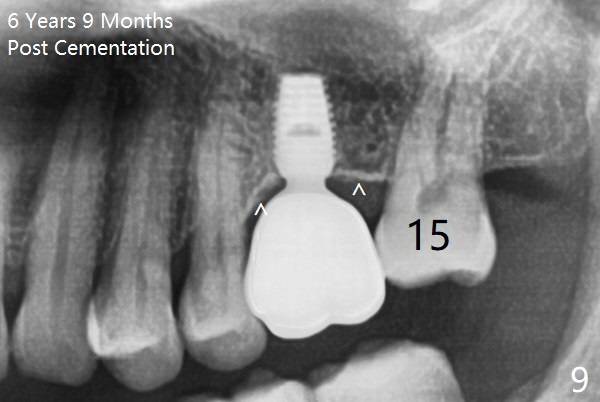

The bone density of the cortex around the implant (Fig.9 ^) is higher than that at #15 and #3, preventing periimplantitis. The pattern of the cortex around the implant changes, as compared to preop (Fig.1) because of deep implant placement.